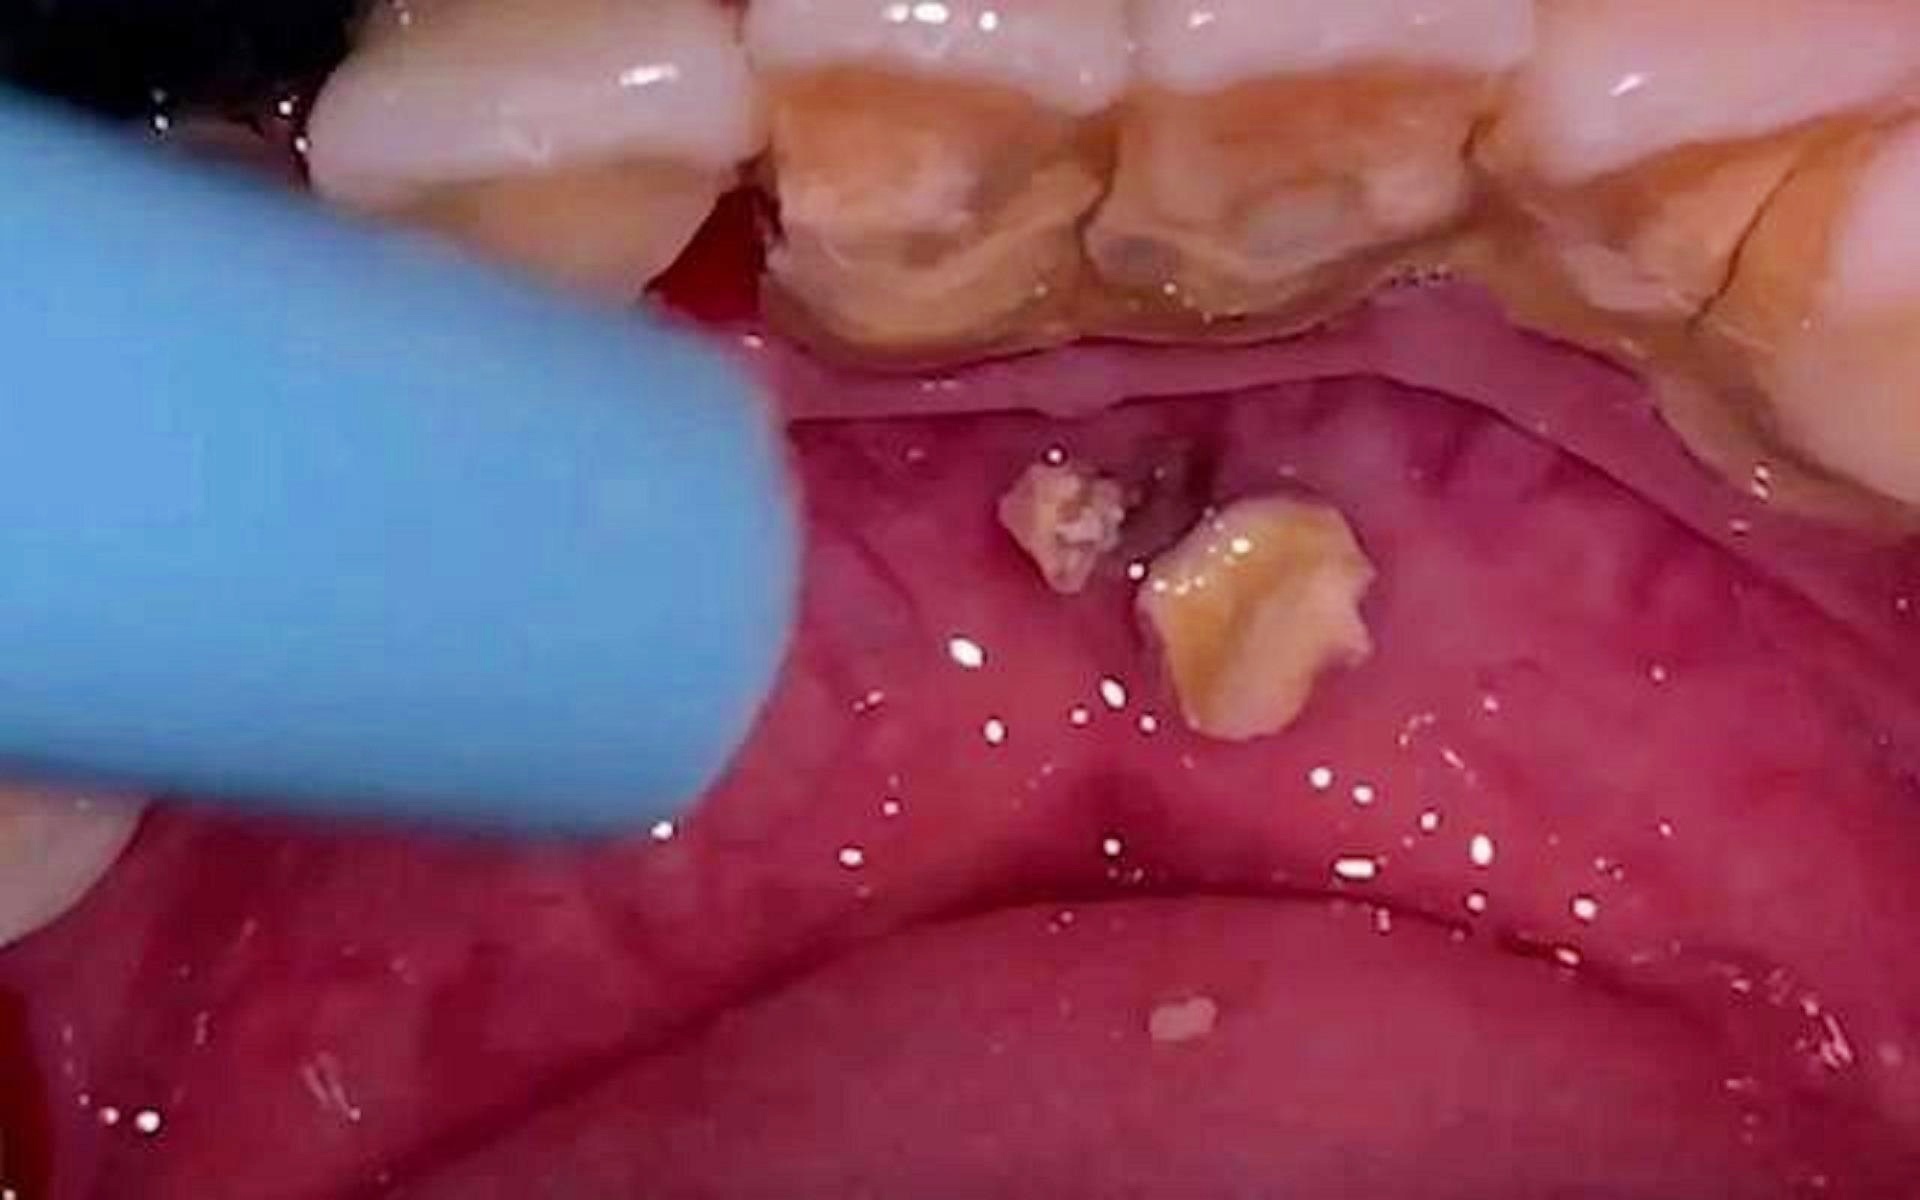

告別牙結(jié)石煩惱,5秒脫落牙結(jié)石的秘密與真相,揭秘,告別牙結(jié)石煩惱,只需5秒輕松脫落的秘密與真相!

摘要:告別牙結(jié)石煩惱,發(fā)現(xiàn)5秒脫落牙結(jié)石的秘密與真相。通過(guò)深入研究,揭示牙結(jié)石形成的原因及傳統(tǒng)治療方法的局限性。本文介紹了一種新的解決方案,能夠在短時(shí)間內(nèi)有效去除牙結(jié)石,同時(shí)保護(hù)牙齒健康。這一發(fā)現(xiàn)為口腔護(hù)理領(lǐng)域帶來(lái)了...